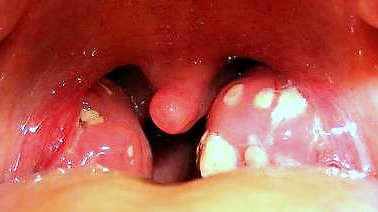

Mononucleosis Infecciosa

Enfermedad del Beso

Manifestaciones Clínicas

síntomas de MI

Diferencial

VIH, CMV, HHV-6, Toxoplasma gondii, Virus de Rubeóla, linfomonocitosis infecciosa aguda, Brucella spp., Leptospirosis, Sífilis, reacciones toxoalérgicas medicamentosas, amigadalitis bacterianas o por adenovirus.